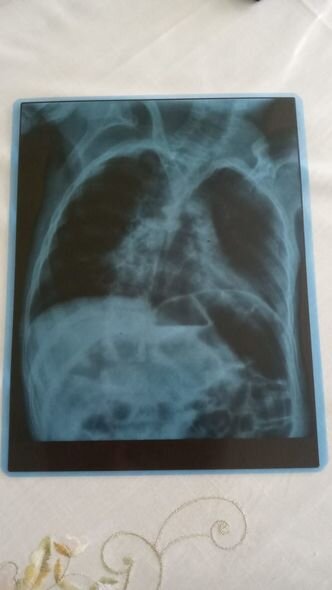

O bildirib ki, övladı serebral iflicdən əziyyət çəkir.

Nərminə Əzizova bildirib ki, Ömərə həm də pnevmoniya diaqnozu qoyulub.

"Öməri soyuq havalarda qətiyyən çölə çıxarmırıq. Qış ərzində ancaq evdə olur. Evin istisinə o qədər öyrəşir ki, çox az müddətə çölə çıxanda xəstələnir. Həkim Ömərə pnevmoniya diaqnozu qoyub. Ömər pnevmoniyaya görə dəfələrlə müalicə alsa da, böyük irəliləyiş olmayıb. Yardımsevər şəxslərin dəstəyi ilə onu həyatda saxlaya bilirik, müalicələrini edirik. Hazırda müalicələrin yarıda qalmaması üçün 150 manata ehtiyacımız var. Ömərin vəziyyəti ilə bağlı mən işləyə bilmirəm, ailəmizdə tək işləyən yoldaşımdır. Ömərdən başqa iki oğlum da var. İnanın, vəziyyətimiz çox ağırdır. Yardımsevər şəxslərdən mənim balama dəstək olmağı, onu bu yolda tək qoymamağı xahiş edirəm".